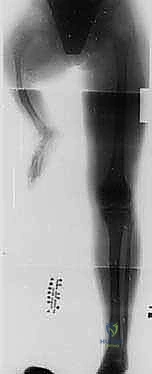

المرحلة الأولى: التخطيط ما قبل الجراحة

تبدأ الرحلة بتقييم شعاعي دقيق (أشعة سينية، وأحياناً رنين مغناطيسي MRI لتقييم الأربطة). يتم قياس التفاوت في طول الأطراف بدقة، وتحديد زوايا الانحراف. يجلس الدكتور هطيف مع العائلة في جلسة استشارية مطولة، يشرح فيها كل التفاصيل، ويجيب على كافة التساؤلات بأمانة طبية مطلقة، مما يزرع الطمأنينة في قلوب الآباء.